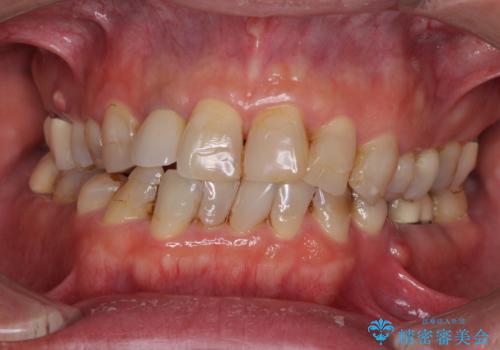

[ 重度歯周病 ] インプラント・義歯による咬合再構築

![[ 重度歯周病 ] インプラント・義歯による咬合再構築の症例 治療前](https://seimitsushinbi.jp/wp/wp-content/uploads/2021/07/0a652e75d5f31b51f66fbb3c46093249-500x350.jpg?v=1626759388)